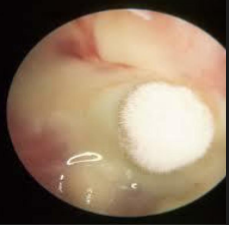

Auricular keloid

Large, round, flesh-colored ball. Common after piercing or trauma.